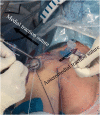

Arthroscopic rotator cuff repair has been shown promising clinical outcomes. However, large to massive rotator cuff tears are difficult to completely repair with appropriate tension because of their size or poor tissue quality. An incomplete repair using the "hybrid technique" is one of way to solve this problem by maximizing the contact area between the tendon and the footprint of greater tuberosity. Additionally, the acellular dermal matrix patch augmentation has emerged as an adjuvant technique to enhance the biomechanical properties to promote healing of the repaired construct. This Technical Note describes arthroscopic incomplete rotator cuff repair using the "hybrid technique" with acellular dermal matrix patch augmentation.